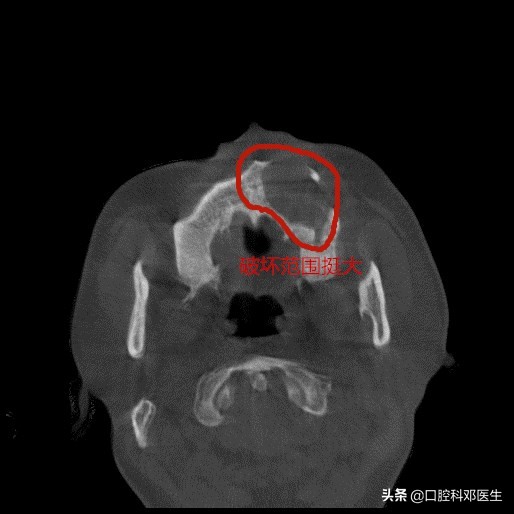

水平位片

接诊的邓医生介绍:这位患者脸肿大是由于左侧上颌骨内一个埋伏多生的牙齿所引起的,由于牙齿无法正常萌出,经过时间的积累,从而诱发囊肿,囊肿一般都不痛不痒,越长越大,像鼓气球一样,逐渐破坏了周围的骨头,如破坏上颌骨前壁,就会突破至软组织,引起脸部肿大;如破坏牙槽骨,则会导致牙齿松动移位,引起牙根吸收疼痛等症状。